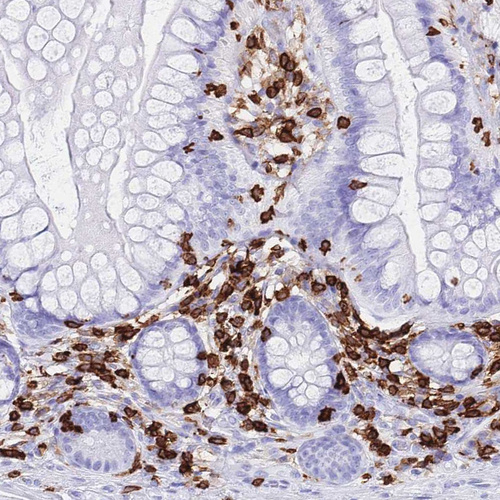

Immunohistochemical staining of human cerebral cortex shows strong cytoplasmic positivity in glial cells.